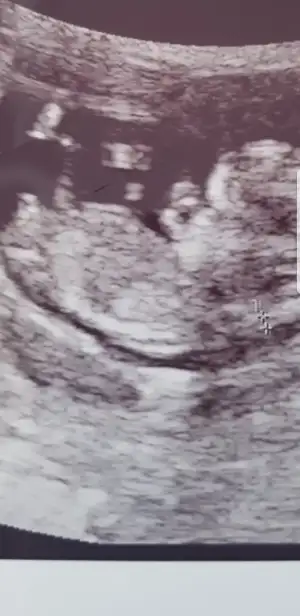

Çok net erkek .11 12 haftalık nub kız görünüyor du. Sonra yükseldi galiba. 12 +5 e kadar güven vermiyor nubYaa 11 hafta yanitti demekki çok paralel görünüyor du varmı 13 hafta bakmak isterim![]()

Kız görünüyorEki Görüntüle 2826055